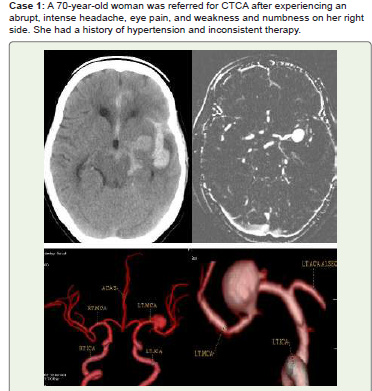

Figure 1:Acute SAH is visible along the anterior interhemispheric fissure,

left sylvian fissure, interpeduncular cistern, left ambient cistern, and left

basal ganglia hemorrhage on noncontrast CT (A). A significant saccular

aneurysm is visible at the left middle cerebral artery (MCA) bifurcation in

CTCA maximum intensity projection (MIP) (B) and 3D volume rendered

images (3D-VR) (C, D). She received medical care and was recommended

for endovascular coiling or surgical clipping.